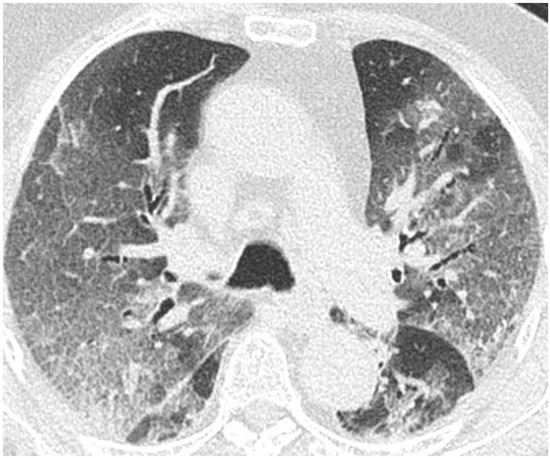

- GGO was defined as hazy increased attenuation of lung with preserved bronchial and vascular margins;

- Consolidation was considered an increase in pulmonary parenchymal attenuation that obscures the airways and vessels;

- Crazy paving was the area of GGO with coexisting thickening of interlobular septae;

- Septal thickening comprised abnormal widening of an interlobular septum or septae;

- Subpleural lines comprised a thin curvilinear opacity of a few millimeters or less thickness usually less than 1 cm from pleural surface and paralleling the pleura.